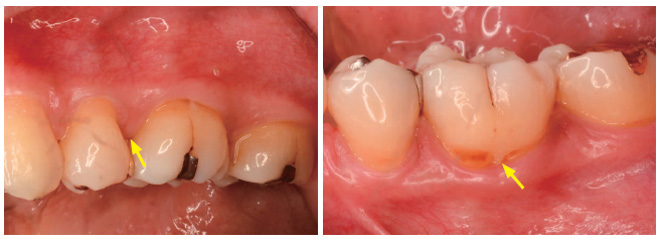

![]() 図T-3-29 歯の形態異常 エナメル突起(エナメルプロジェクション) 上下顎第1 大臼歯部にみられたエナメル突起(エナメルプロジェクション〈矢印で示した突起部〉). 根分岐部の発生期の先天異常であるため,左右対称にみられる. |

![]() 図T-3-29 歯の形態異常 エナメル突起(エナメルプロジェクション) 下顎第1 大臼歯部にみられたエナメル突起(エナメルプロジェクション〈矢印で示した突起部〉). 根分岐部の発生期の先天異常であるため,左右対称にみられる. |